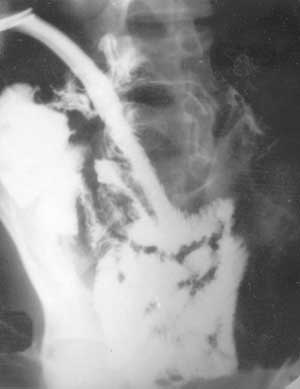

Рис. 4. Дистальная постстомальная энтерография при петлевой еюностоме. Контрастированы подвздошная кишка, илеоцекальный переход и слепая кишка.